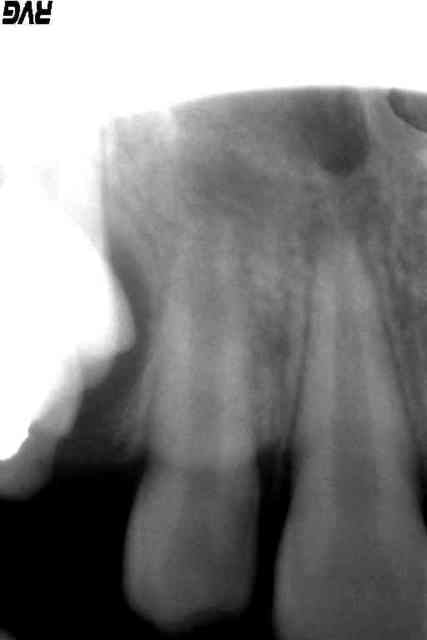

nous sommes donc au moins 2 à voir cette image radio claire, donc cette ENORME LESION et pensez qu'il faut intervenir.

3° Radiographie : jugez-en vous-même, je ne vois pas d'image apicale flagrante pour 22. Les apex de 12 et 22 sont comparables.